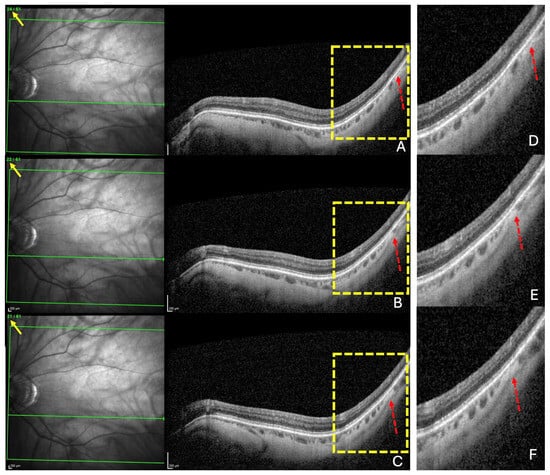

2.1.2. OCT Analysis

- A search for choroidal thinning in 3 locations in the temporal part of the posterior pole.

- Measurement of the choroidal thinning and distance from fovea to thinning.